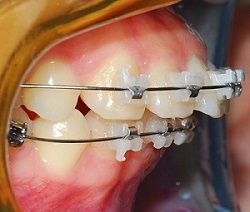

치아 사진 먼저 보여드릴게요

여기도 아주 조금 남은 공간이 보이시나요?

찾기 힘들정도로 조금 남앗어요ㅎㅎㅎ

윗 니 발치공간이 다 닫힐 거라고 예상했던 것과 달리

0.5mm 정도 발치공간이 남았구

아래는 좀 더 많이 남았어요